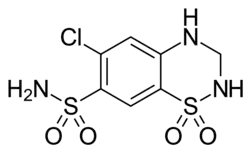

Treatment may include lifestyle changes, medications, and surgery.[3] Medications used may include ACE inhibitors.[3] Often multiple blood pressure medications; however, are required.[3] If this is not sufficient angioplasty or endarterectomy may be performed.[3]